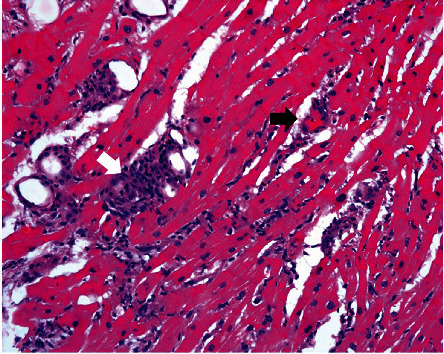

68岁女性,终末期心力衰竭,到医院行心脏移植手术。她在14个月前被诊断为失弛缓症,并经常注射肉毒杆菌毒素治疗。她在入院当天接受了原位心脏移植手术,几天后拔管。她出现难治性恶心和呕吐。她的第一次心内膜活检显示中度,接近严重排斥反应。她接受了大剂量静脉注射类固醇治疗。随访活检时的x线检查显示食管未消化的药丸,远端狭窄,因此无法给予免疫抑制治疗。本病例强调贲门失弛缓症是急性排斥反应的病因及其潜在的治疗方法。

A 68-year-old female with end-stage heart failure presented to the hospital for heart transplant. She was diagnosed with achalasia 14 months prior and treated with frequent botulinum toxin injections. She underwent orthotopic heart transplant on the day of admission and was extubated a few days later. She developed intractable nausea and vomiting. Her first endomyocardial biopsy revealed moderate, approaching severe rejection. She was treated with high-dose intravenous pulse steroids. Fluoroscopy at the time of follow-up biopsy showed undigested pills in her esophagus with narrowing at the distal end and thus failure to deliver immunosuppressive therapy. This case highlights achalasia as an etiology for acute rejection and its potential management.